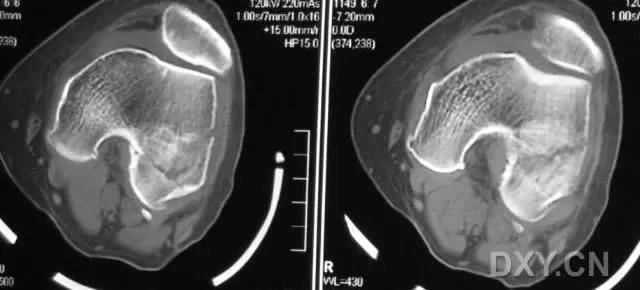

8. Segond 骨折和反向 Segond 骨折

(1)Segond 骨折

是发生在胫骨平台外侧的垂直撕脱性骨折。这种骨折在前后位 X 线片上显示最佳。屈曲位时膝关节受到内旋暴力作用,导致皮质骨撕脱性骨折,这种骨折常发生在运动员身上。

常引起股骨内髁和胫骨平台后内侧骨挫伤,75%~100% 的患者伴前交叉韧带断裂,33% 的患者伴外侧半月板损伤。

一位足球运动员的 Segond 骨折。A 正位片示关节线下方胫骨外侧皮质撕脱(箭头)。B MRI 冠状位 T1 加权像示附着于髂胫带的骨折碎片(空箭头)(来源:Radiol Clin N Am 53 (2015) 737–755,YU,Ohio)

(2)反向 Segond 骨折

胫骨平台内侧皮质骨撕脱性骨折,被称为内侧 Segond 骨折或反向 Segond 骨折。这种骨折的旋转机制与 Segond 骨折相反,该骨折与后交叉韧带断裂及内侧半月板损伤相关。

一位足球运动员的反向 Segond 骨折。A 正位片示关节线处的胫骨内侧见一细小骨折片(箭头)。B MRI 冠状位 T1 加权像示骨折片出现在内侧副韧带关节囊附着处(方框)(来源:Radiol Clin N Am 53 (2015) 737–755,YU,Ohio)